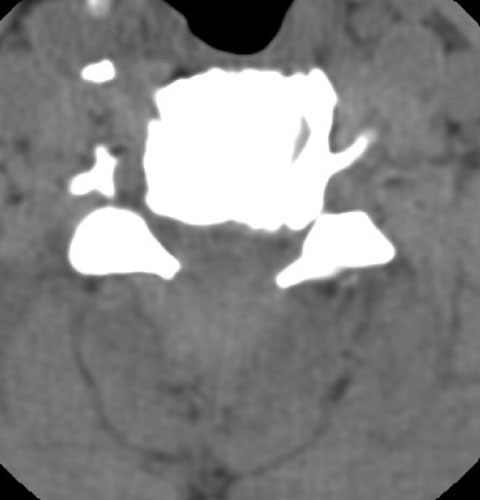

63 y.o. male with severe spinal stenosis and associate myelopathy in both hands and feet. Patient underwent laminectomy from C2-C7. 1 day after initial operation patient with severe numbness to left arm. Then, patient became unable to move either leg within 2 hours after that initial complaint. A Stat non-contrast CT was ordered.

Axial CT demonstrates laminectomy defect at the level shown. A hyperdense fluid collection with some air bubbles  is identified consistent with an epidural hematoma, extending from the C2-3 level to C7-T1 .